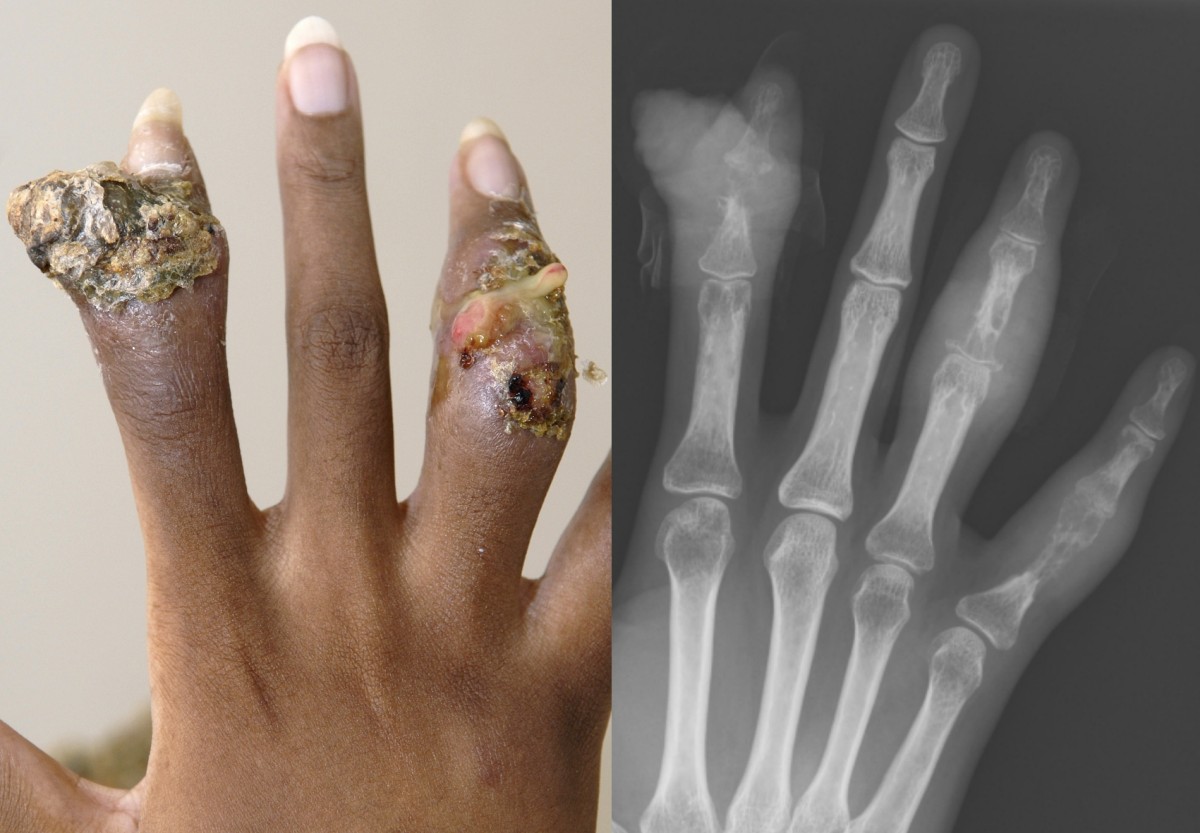

bot sarcoidose long sarcoidose PA sarcoidose

- Bot <1% (ophelderingen, lacy-like appearance, destructie)

Sarcoidose van de huid:

Bij gemiddeld zo'n 20-25% van de patiënten met sarcoidose is de huid aangedaan. De huidlesie die het sterkst geassocieerd is met sarcoidose is erythema nodosum. Dit kan gevonden worden tijdens het beloop van sarcoidose, maar ontstaat echter vaker bij het begin van de ziekte. De huidlesies kunnen worden geklassificeerd als specifiek en niet-specifiek, waarbij de specifieke laesies granulomateus zijn en de niet-specifieke reactief. Specifieke sarcoidlesies manifesteren zich maculopapuleus, noduli, plaques, subcutane noduli, littekeninfiltratie en als lupus pernio. Er bestaat geen relatie met de ernst of uitgebreidheid van ziekte, behalve dat erythema nodosum gezien wordt bij een vorm van sarcoïdose die zelflimiterend is.

Chronische huidsarcoïdose manifesteert zich als niet pijnlijke en niet-jeukende plaques en subcutane noduli rond de haarlijn, oogleden, oren, neus, mond en de strekzijde van de extremiteiten. Annulaire plaques komen voor op het voorhoofd en leiden tot litteken en alopecia. Noduli worden later in het ziekte proces gevonden. Oude littekens kunnen ook na jaren geïnfiltreerd worden bij sarcoidose. Een veranderd litteken kan duiden op activiteit van de sarcoidose. De reden van infiltratie is onbekend. Lupus pernio is de meest karakteristieke huidlesie bij sarcoidose en duidt op fibrose.